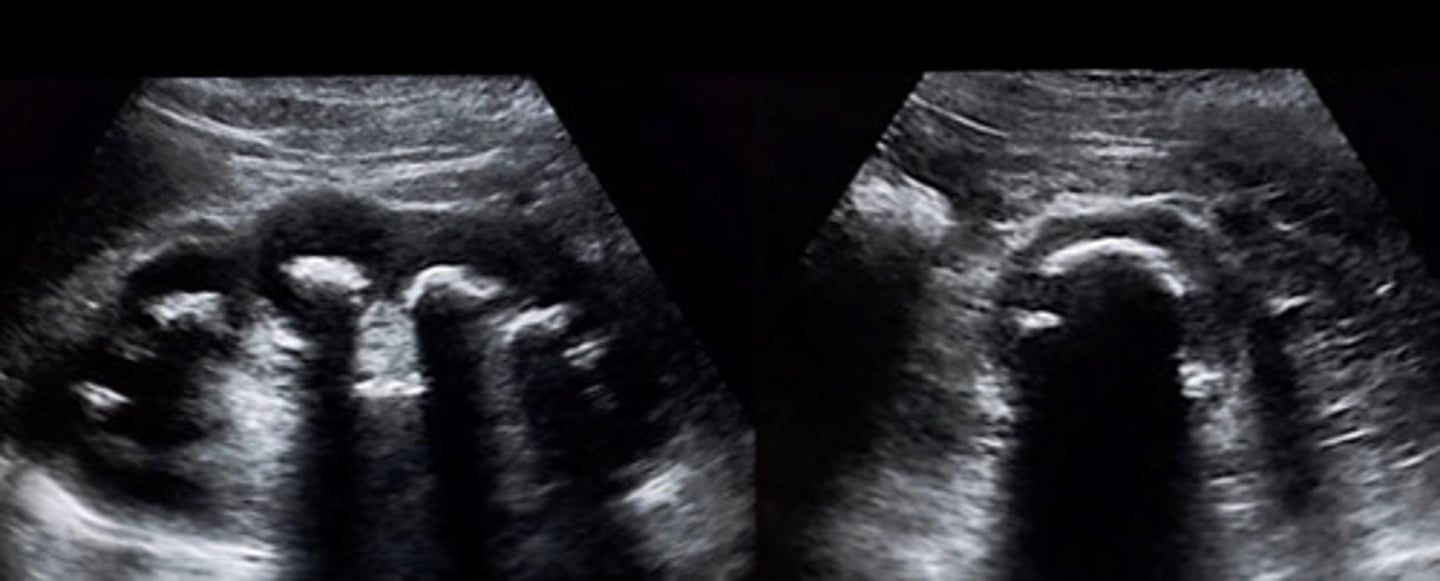

Grade 1 hydro

What does this image show

New cards

<p>What does this image show</p>

Separation of entire central sinus and club calyces

Describe the appearance of grade 2 hydro

Grade 2 hydro